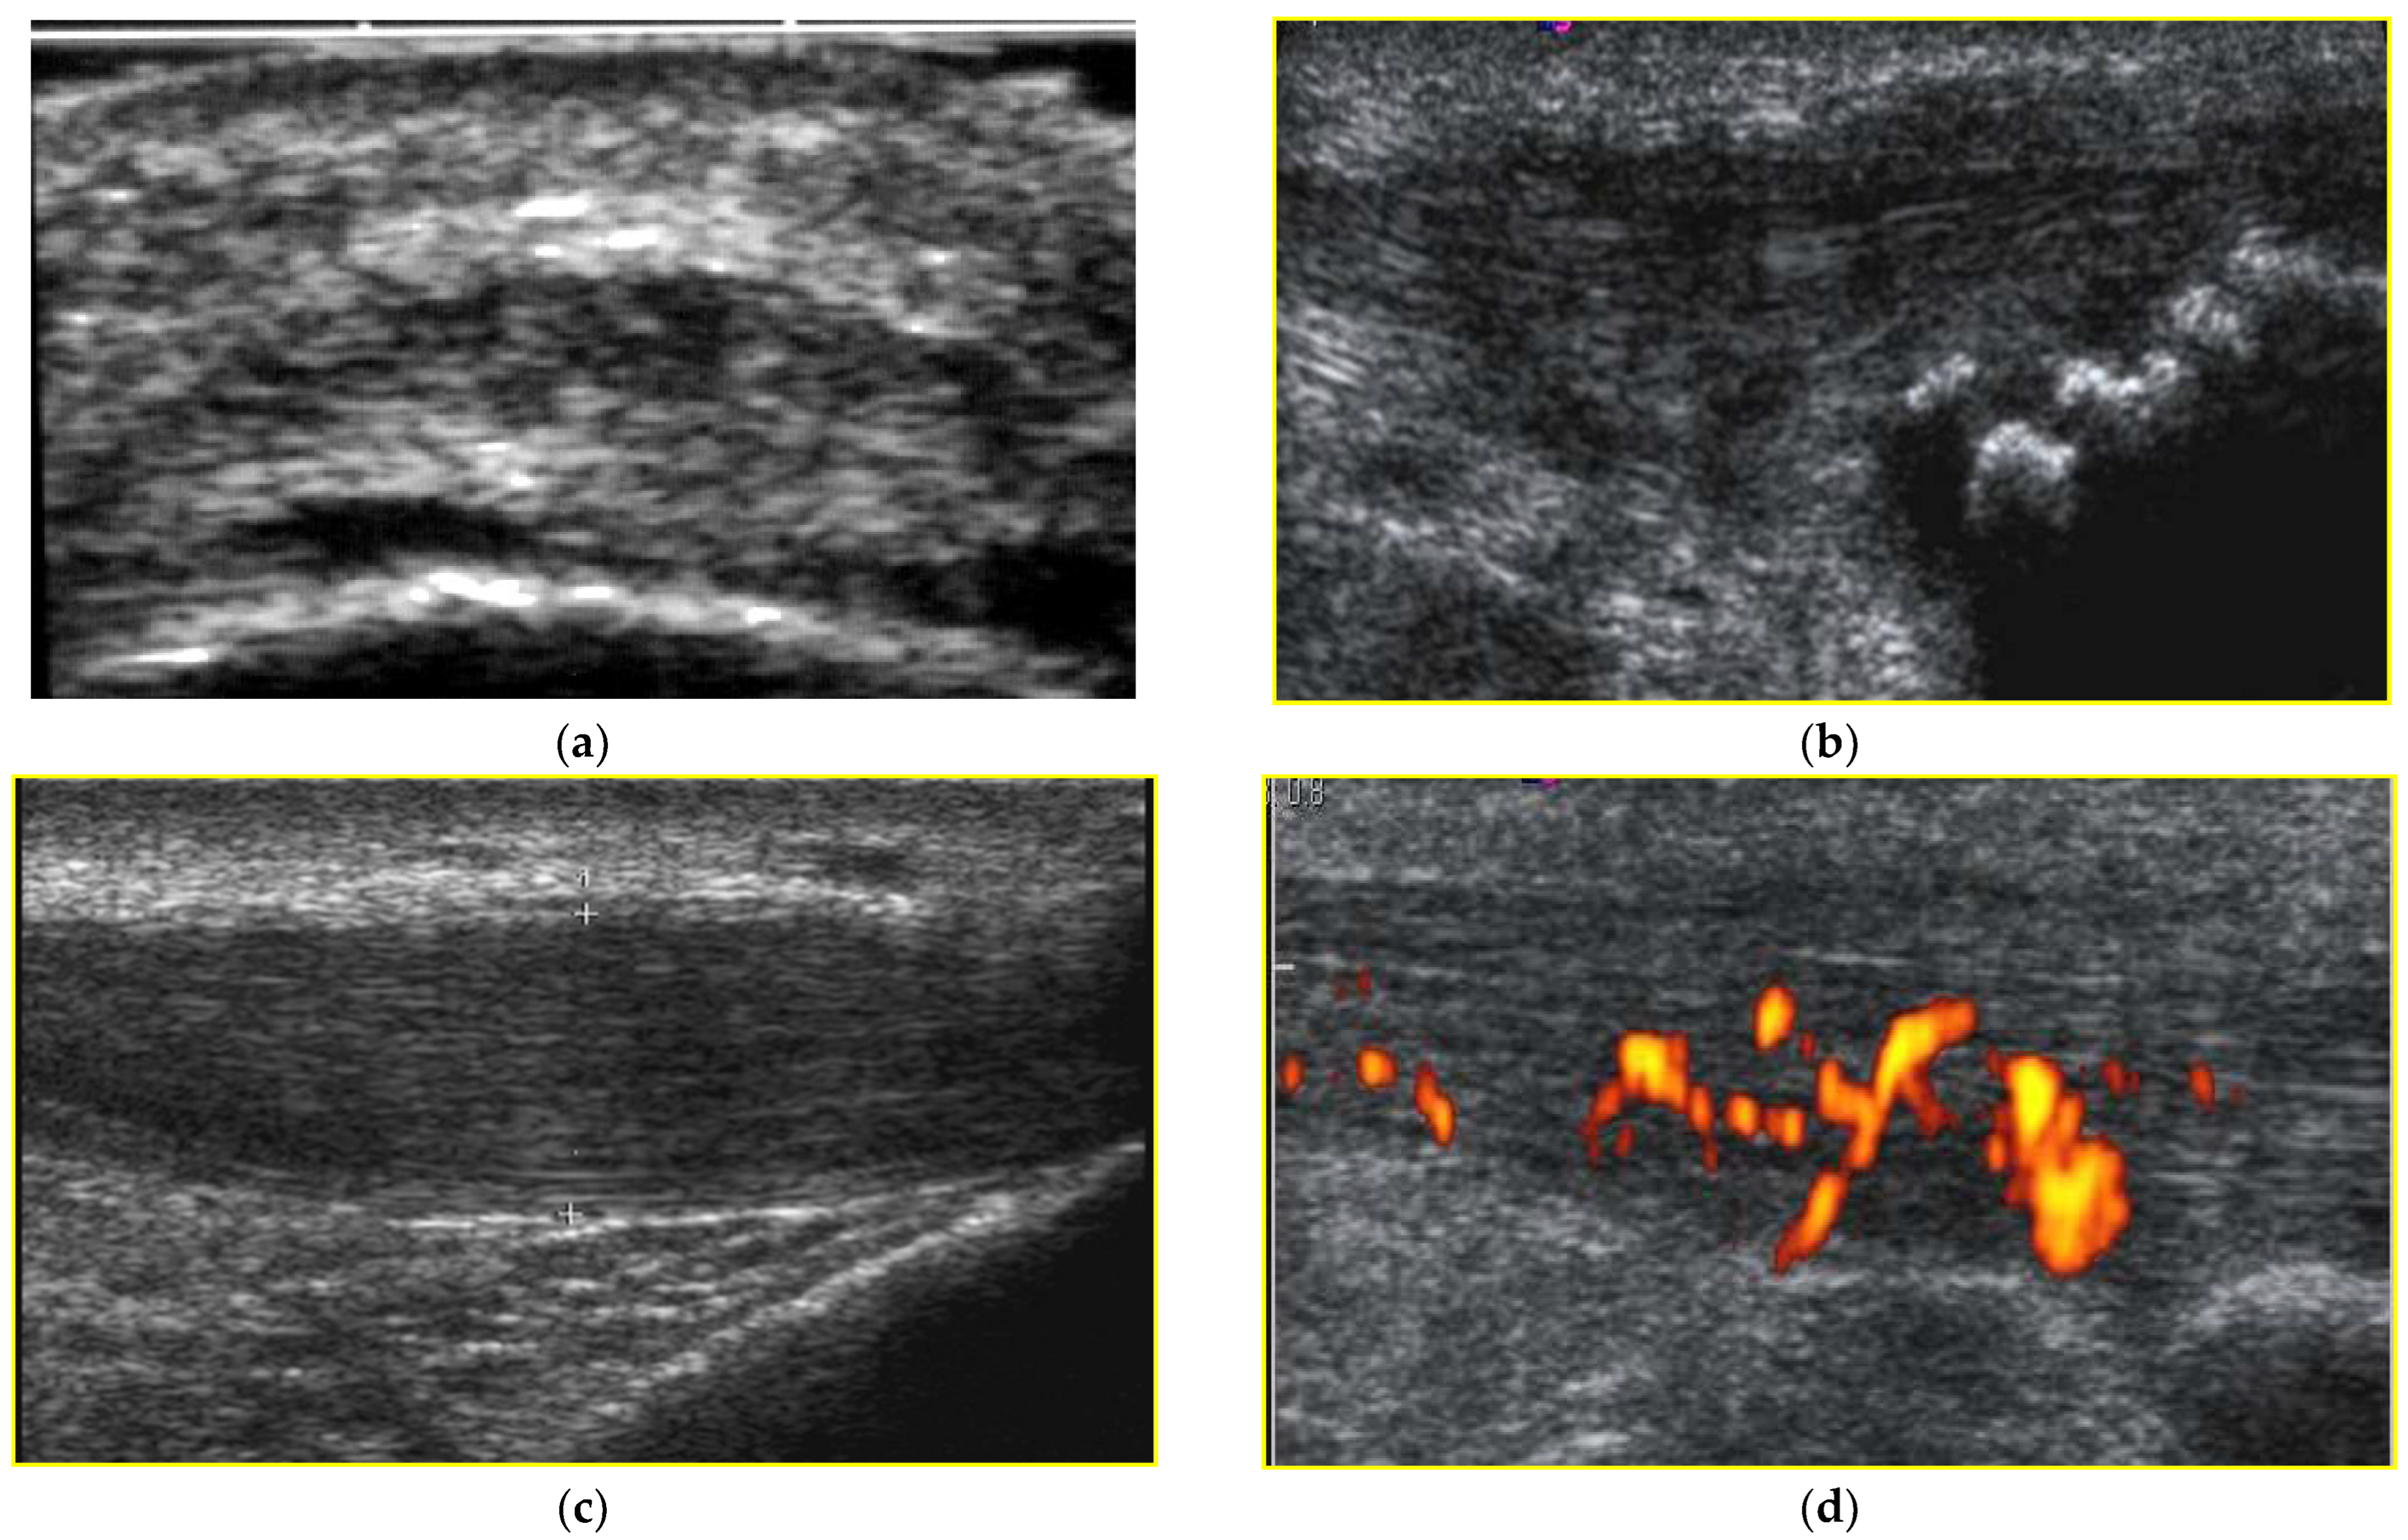

2.2. Ultrasound Assessment

| Echostructural Alteration | Signs of Hyperemia on Power-Color Doppler |

| Grade 0—normal tendon | Grade 0—no visible new vessels |

| Grade 1—slight echostructural alteration | Grade 1—one to two new vessels |

| Grade 2—moderate echostructural alteration | Grade 2—few vessels/low blood flow |

| Grade 3—marked echo structural alteration and degeneration | Grade 3—many vessels/important blood flow |